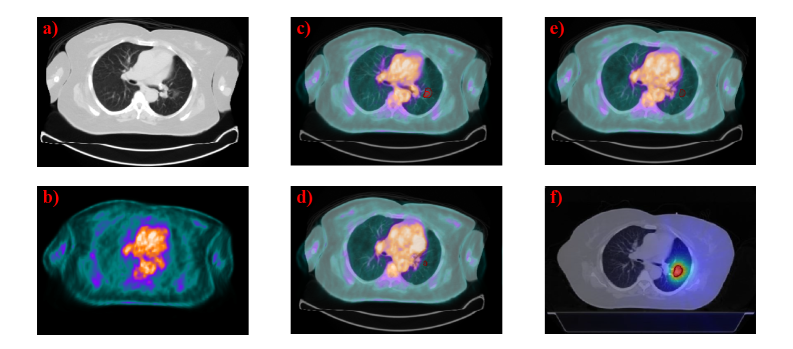

To concretize the challenges mentioned above and motivate our design choices, Figure 1 presents a representative case. The CT (Fig. 1a) and PET (Fig. 1b) provide complementary anatomic and metabolic cues, while the fused image (Fig. 1c) highlights the discrepancy between the IGTV (dark red) and GTV (light red) contours. The marginal slices in Figs. 1d and 1e illustrate the confounding effect of high SUV uptake in neighboring organs (e.g., the heart) and low tumor uptake, which obscures lesion borders on PET and hampers robust delineation. Finally, Fig. 1f visualizes the radiation therapy dose distribution planned on the PTV, which is a 5 mm uniform expansion from IGTV to account for delivery uncertainty and patient setup error, underscoring the clinical impact of precise IGTV definition.

Refer to caption

Figure 1: Multimodal illustration of IGTV versus GTV and radiotherapy planning. (a) CT image; (b) PET image; (c) fused PET/CT image with IGTV (dark red) and GTV (light red) contours; (d,e) IGTV marginal slices with high organ SUV and low tumor uptake; (f) radiation therapy dose distribution derived from the IGTV contour.